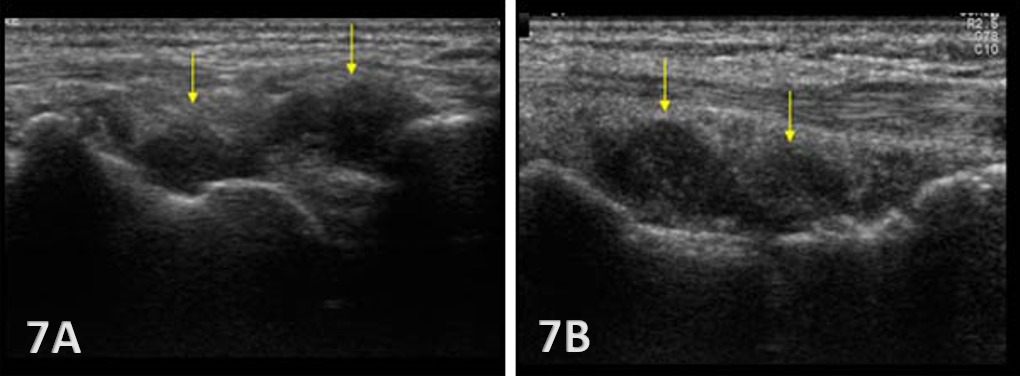

Normal Sonographic Appearance

Typically, the radiocarpal joint is viewed in both the LAX and SAX. Typically, there is no joint effusion; therefore, the joint recess is collapsed or barely visible on ultrasound. The capsule should be thin and not distended. The dorsal ligaments are normally continuous and should exhibit a normal fibrillar pattern, indicating they are intact and healthy. The synovium is typically visualized as a very thin echogenic line, with no synovial hypertrophy. The articular surfaces of the radius and the carpal bones should include uniform anechoic or hypoechoic cartilage layers and demonstrate smooth, continuous hyperechoic cortical lines with no physical breaks or breaches.

Anechoic or hypoechoic joint effusion and/or synovitis (synovial hypertrophy) and cysts within the joint.

Joint effusion is somewhat compressible and mobile when transducer pressure is applied to the area. This is different from synovitis, which appears as hypoechoic or isoechoic, non-compressible tissue within the joint recess. Synovitis may be associated with conditions such as rheumatoid arthritis, psoriatic arthritis, or other inflammatory arthropathies. Lastly, a ganglion cyst may appear as a well-defined, round or lobulated cystic structure with anechoic or hypoechoic internal contents. The cyst will usually have a small, smooth wall and exhibit posterior acoustic enhancement. These cysts will typically be minimally or non-compressible and painful.

Early Detection of Injury / Accurate Injury Grading: MSKUS can detect small anechoic or hypoechoic fluid collections in the radiocarpal recess that may be invisible to the naked eye. Finding this early will help guide treatment planning. Additionally, small ligament sprains or partial tears may be seen on ultrasound as irregular loss of normal fibrillar patterns.

Dynamic Functional Testing: Rehabilitation professionals can use MSKUS to dynamically stress the tissues with gentle wrist motion to reveal instability or soft tissue impingement between bones or abnormal findings such as cysts.